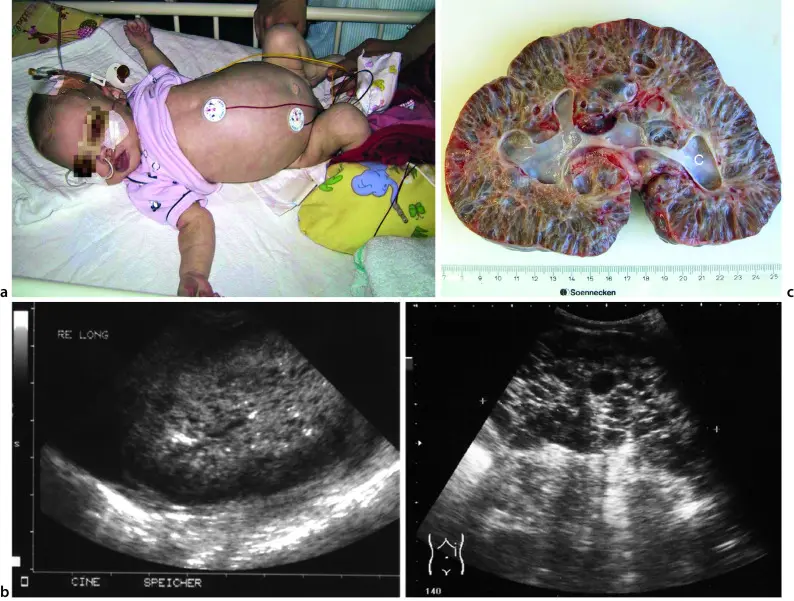

- Ultraschalluntersuchung: Eine Ultraschalluntersuchung kann die Nieren und die Harnwege sichtbar machen und auf Auffälligkeiten wie Nierensteine oder Zysten hinweisen.

- Computertomographie (CT): Eine CT kann detaillierte Bilder der Nieren und der Harnwege liefern.